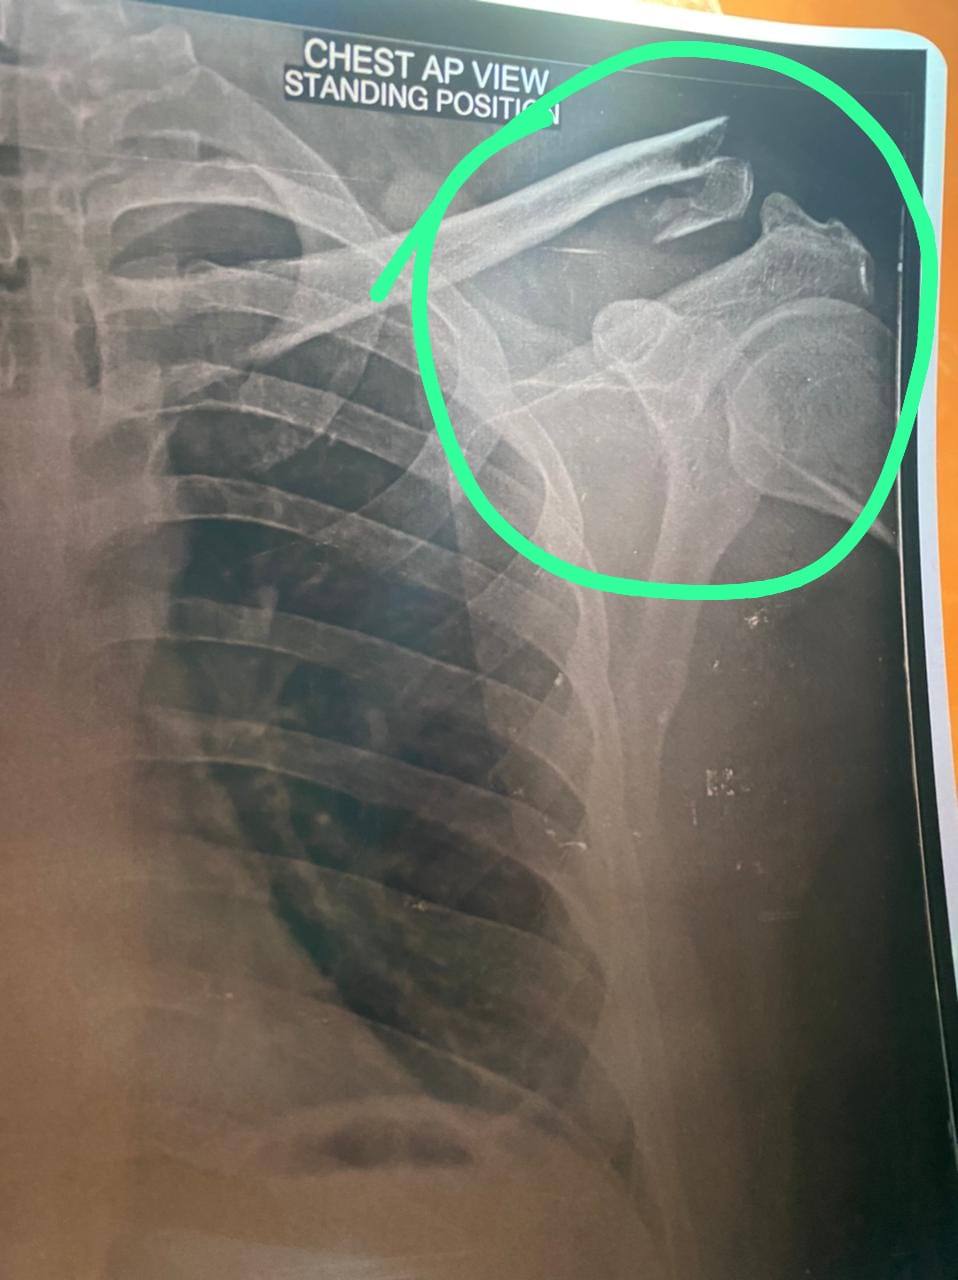

Bike se gir jane se ac joint break ho gaya hai accident ko one week ho gaya hai leasure opration me kitna charge lagega plz bataye